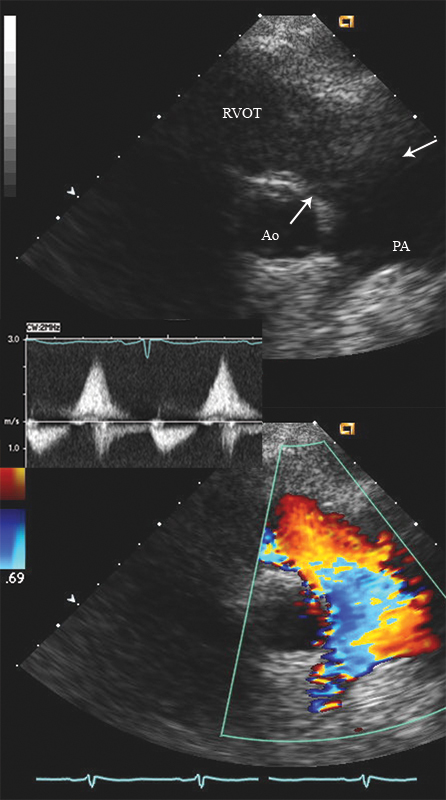

فحوصات تشخيصية لبعض امراض القلب والشرايين التاجية